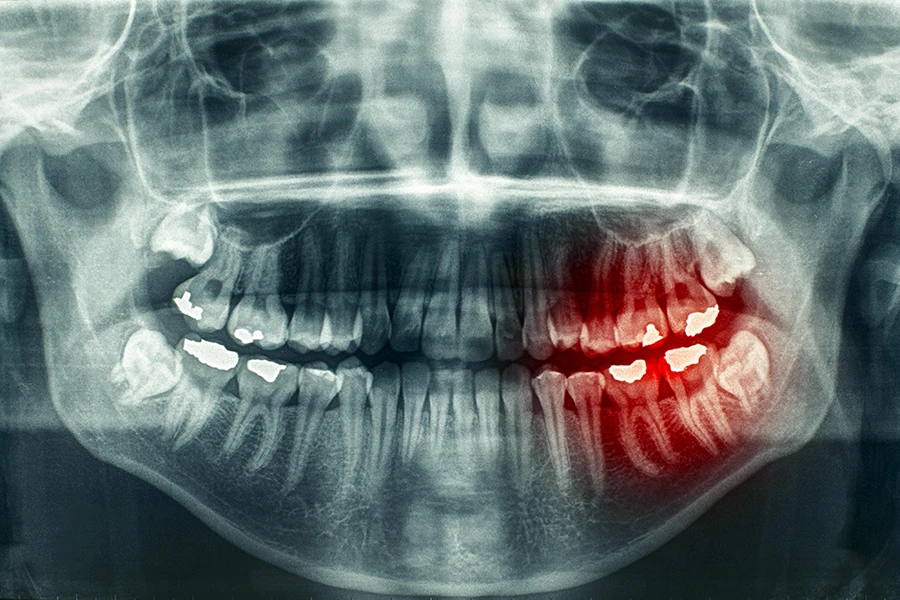

عکس OPG، که مخفف Orthopantomogram است، یک نوع تصویربرداری پانورامیک دندانی است که تصویر واضح و جامعی از تمام دندان ها، هر دو فک، استخوان فک و مفصل گیجگاهی-فکی ارائه می دهد. این تصویربرداری برای تشخیص دقیق مشکلات دندانی و فکی مانند پوسیدگی دندان ها، عفونت های دندانی، شکستگی ها و سایر مشکلات مرتبط با فک و صورت استفاده می شود.

دندانپزشکان از عکس او پی جی برای شناسایی مشکلاتی که ممکن است در معاینه دهانی قابل مشاهده نباشند، استفاده می کنند. این عکس به آنها کمک می کند تا وضعیت دندان ها، ریشهه ا، محل قرارگیری فک و ترکیب استخوان صورت بیمار را ببینند و برنامه ریزی درمان مناسب را برای بیماران خود انجام دهند. همچنین، عکس OPG می تواند برای برنامه ریزی های جراحی، مانند قرار دادن ایمپلنت دندان و کارهای زیبایی مانند اصلاح طرح لبخند استفاده شود.